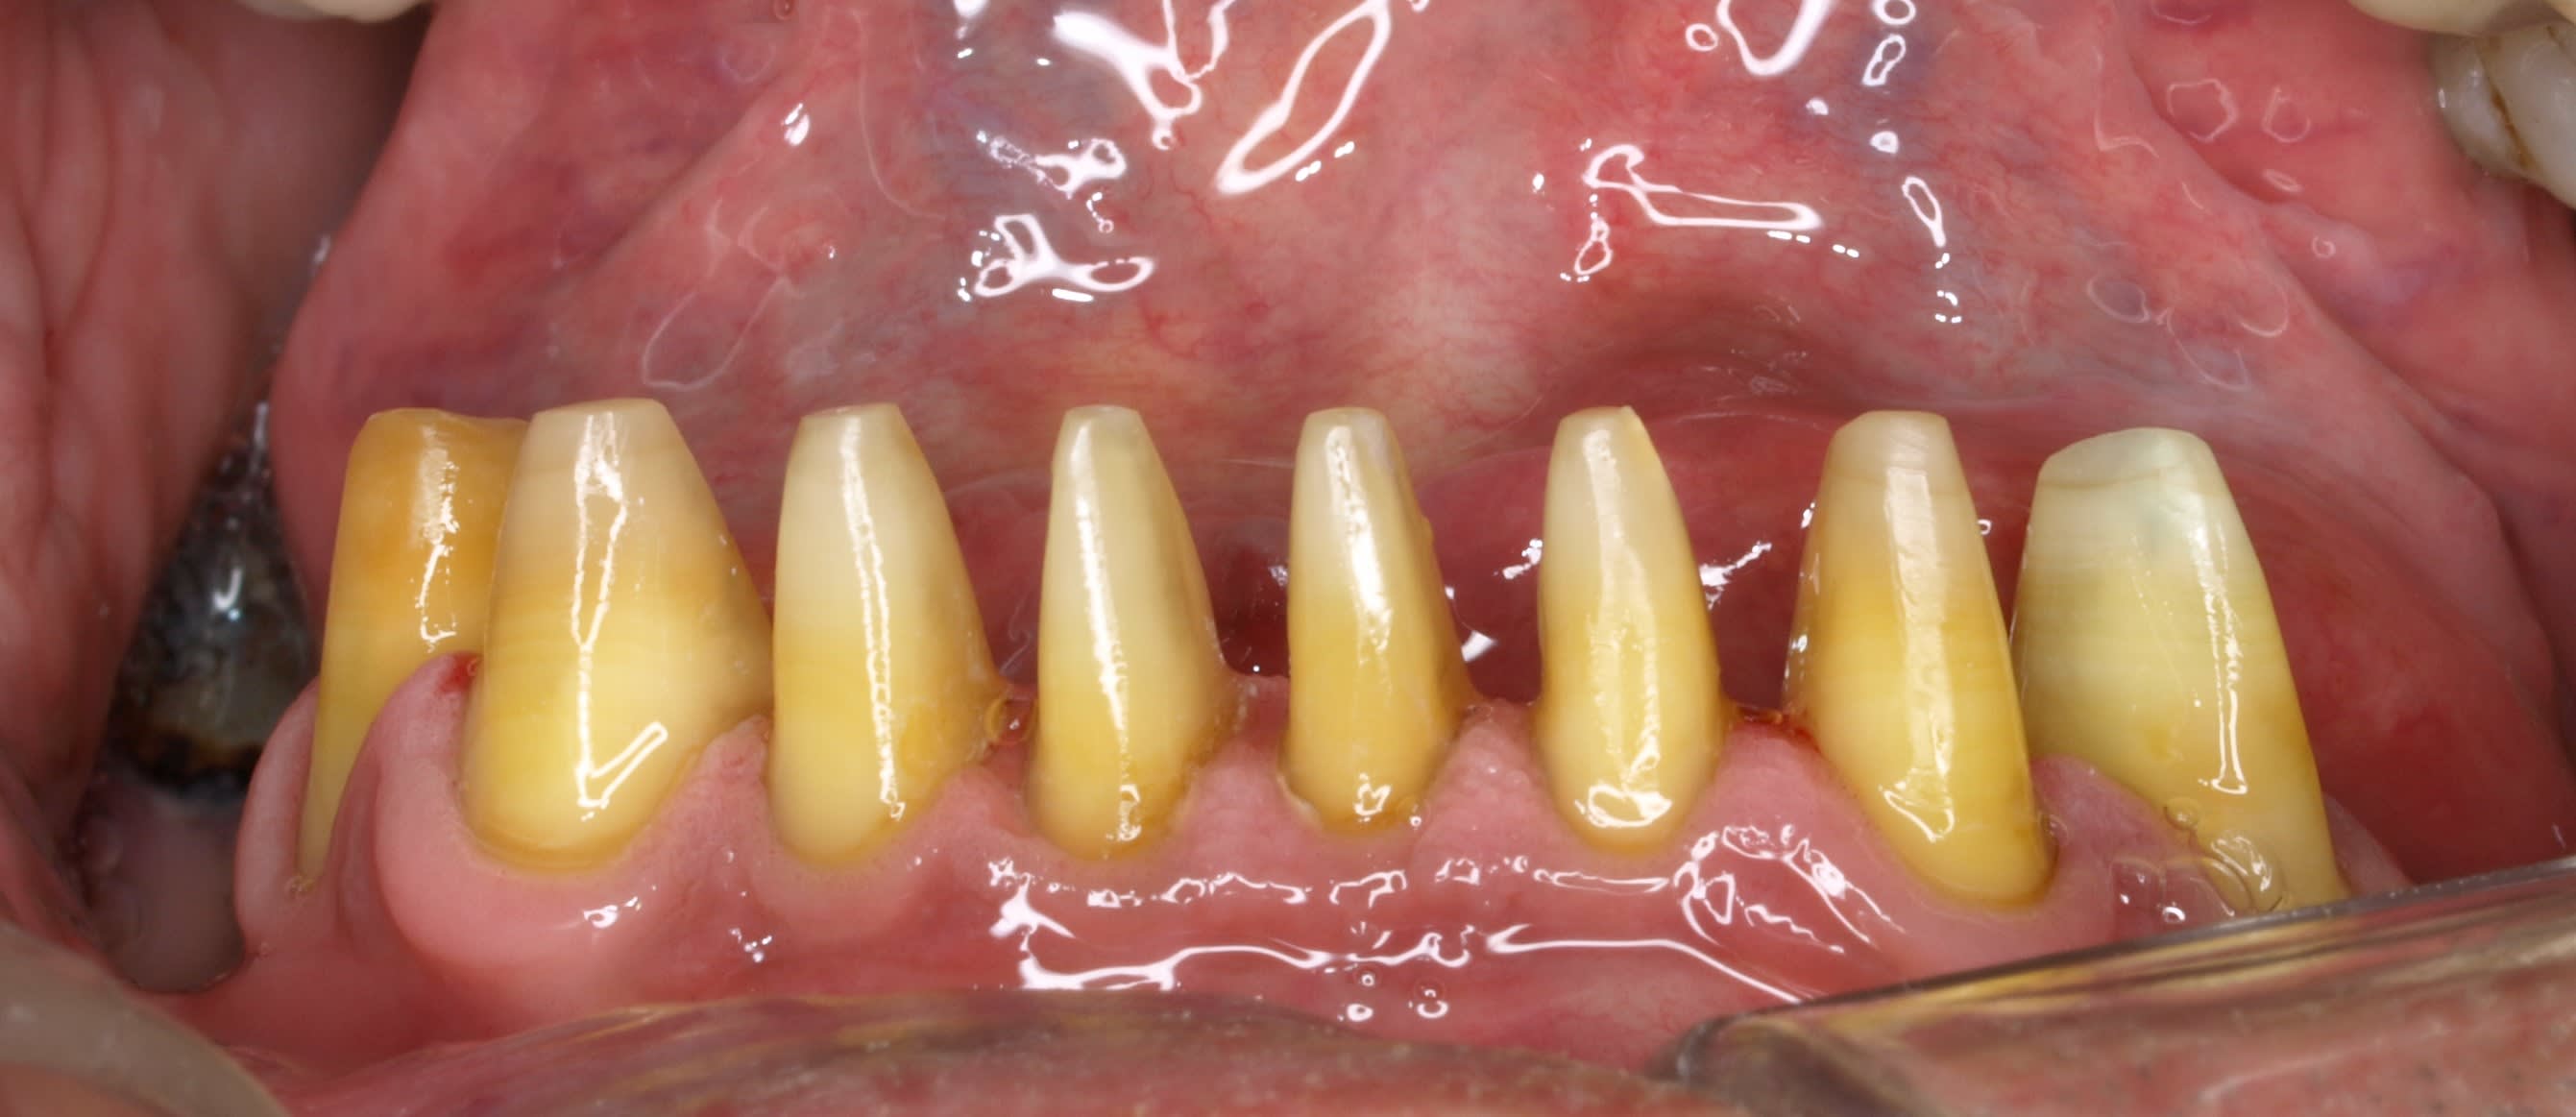

Empreitne dans la foulée. COMME D'HAB.

maintenant , si tu commences à vouloir jouer dans du sérieux , je pense que la wash ou la ouacheu , ç est plus approprié :-)))